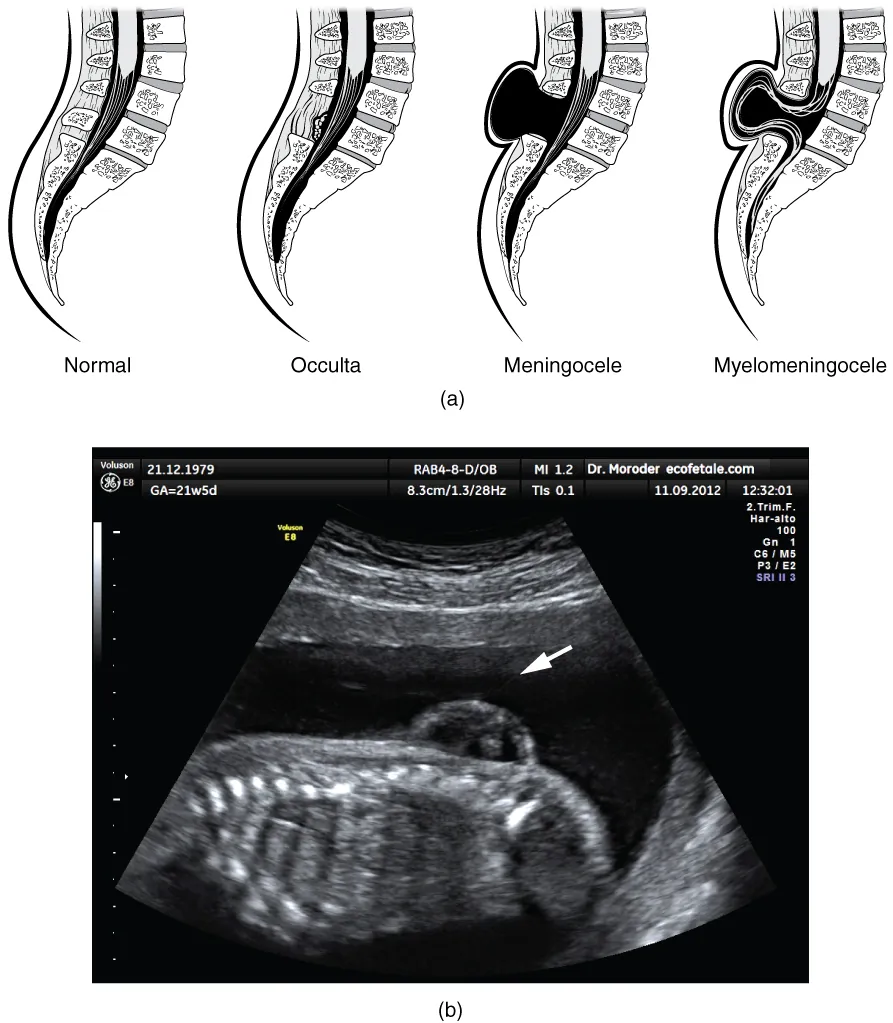

There are three classes of this disorder: occulta, meningocele, and myelomeningocele (Figure 13.5). The first type, spina bifida occulta, is the mildest because the vertebral bones do not fully surround the spinal cord, but the spinal cord itself is not affected. No functional differences may be noticed, which is what the word occulta means; it is hidden spina bifida. The other two types both involve the formation of a cyst—a fluid-filled sac of the connective tissues that cover the spinal cord called the meninges. “Meningocele” means that the meninges protrude through the spinal column but nerves may not be involved and few symptoms are present, though complications may arise later in life. “Myelomeningocele” means that the meninges protrude and spinal nerves are involved, and therefore severe neurological symptoms can be present.

Often surgery to close the opening or to remove the cyst is necessary. The earlier that surgery can be performed, the better the chances of controlling or limiting further damage or infection at the opening. For many children with meningocele, surgery will alleviate the pain, although they may experience some functional loss. Because the myelomeningocele form of spina bifida involves more extensive damage to the nervous tissue, neurological damage may persist, but symptoms can often be handled. Complications of the spinal cord may present later in life, but overall life expectancy is not reduced.

This figure shows the spinal cord in spina bifida, a birth defect. In the top panel, four different spinal cords are shown. The leftmost panel shows a normal spinal cord. The remaining panels show the spinal cord in various stages of spina bifida. The bottom panel shows an ultrasound image, with a white arrow showing the region of the defect.

Figure 13.5 Spinal Bifida (a) Spina bifida is a birth defect of the spinal cord caused when the neural tube does not completely close, but the rest of development continues. The result is the emergence of meninges and neural tissue through the vertebral column. (b) Fetal myelomeningocele is evident in this ultrasound taken at 21 weeks.